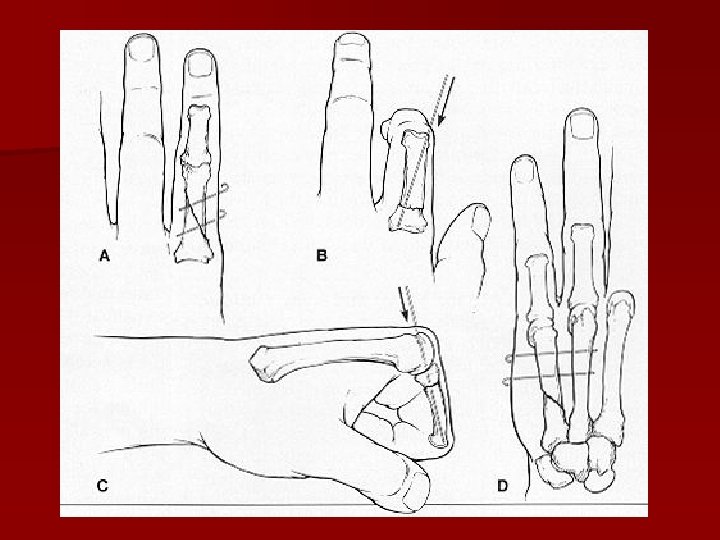

Fractură col metacarpian – OS broşe K.

Fractură oblică col metacarpian

Fractură transversă diafiză metacarp

Fractură oblică diafiză metacarp